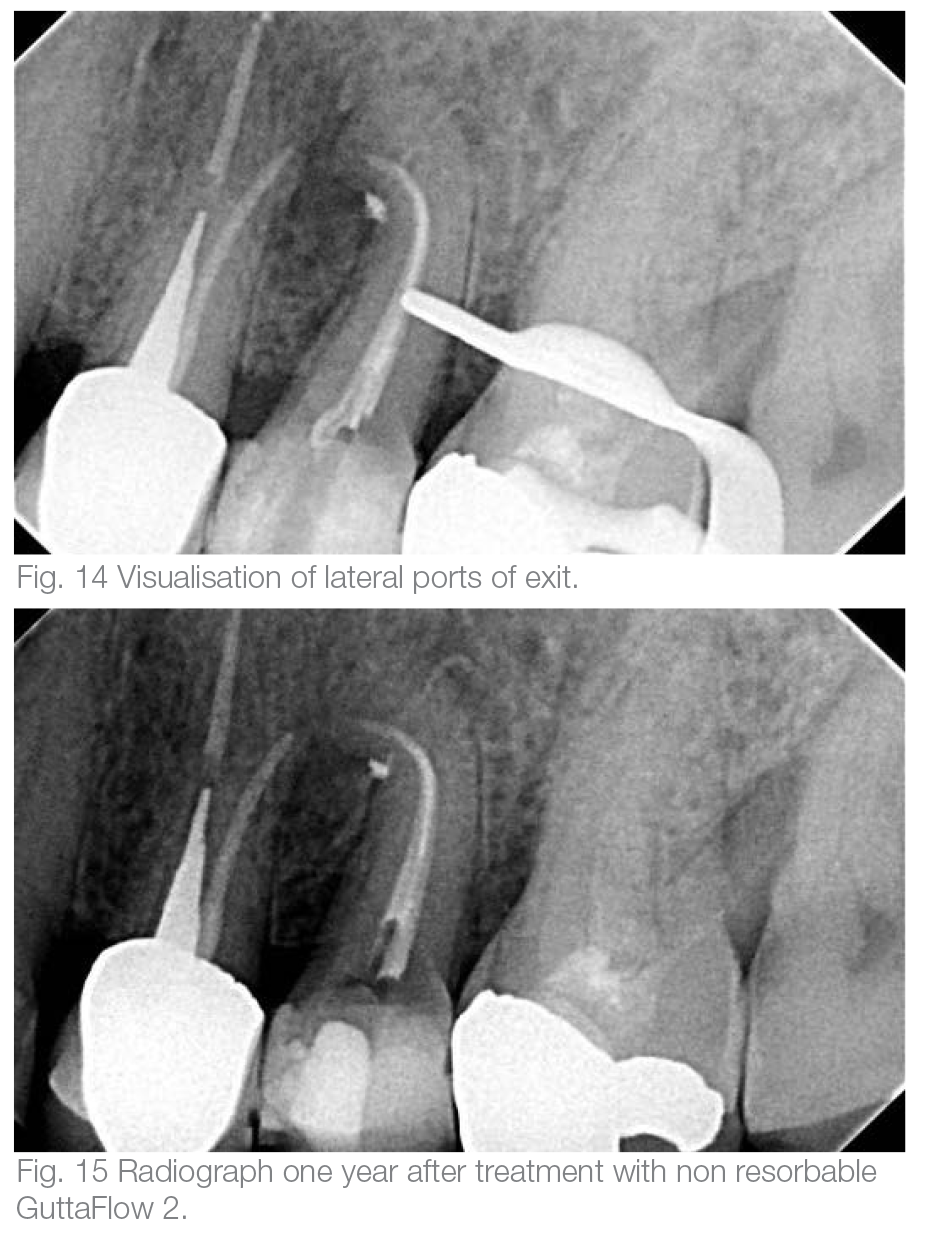

The tooth was restored with a fiber post, a composite built up and a PFM crown. In the final radiographic image of the tooth right after the RCT, the lateral ports of exit could be visualised (Fig. 14). One year after the treatment, the follow-up radiograph revealed complete healing. The nonabsorbable GuttaFlow 2 could be detected unaltered in the lateral portals of exit (Fig. 15). The buccal and occlusal clinical view of the tooth and soft tissues can be seen in Figures 16 and 17.